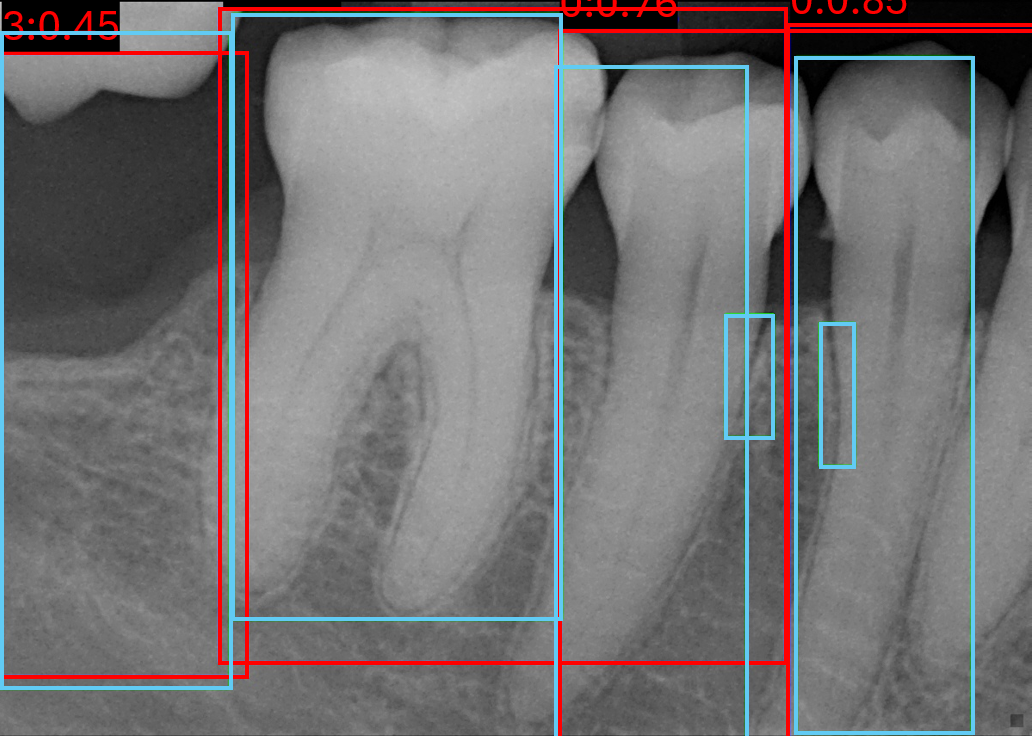

We conducted comprehensive annotation of the collected radiographs, divided into four steps. These include annotating Bone Level Keypoints (BLK) for each tooth, identifying the Teeth Bounding Box (TBB) with tooth orientation, annotating ARR keypoints, and widened PLS bounding boxes. Figure 1 provides visual examples of the annotations.

Refer to caption

Figure 1: Three images containing example annotations of the collected keypoints and rotating bounding boxes.

Figure 7 shows qualitative examples of detection performance on the validation set. Both models generally localise tooth boundaries with high precision, although analysing RTMDet performance indicates occasionally grouping of multiple teeth within a single bounding box, while still often retaining the appropriate number of boxes per tooth in the image. In some cases, both methods detect teeth absent from the annotations, suggesting improved actual sensitivity relative to the ground truth but at the cost of reduced quantitative precision.

(a) Image 119 YOLOv8

(b) Image 120 YOLOv8

(c) Image 171 YOLOv8

(d) Image 119 RTMDet

(e) Image 120 RTMDet

(f) Image 171 RTMDet

Figure 7: Six validation images with overlaid bounding box results, where light blue is the target boxes and red is the predicted boxes.

Both models consistently fail on PLS classes, despite its higher sample size compared to ARR and triple root classes, shown in Figure 7(b) and Figure 7(e). This limitation is likely due to the visual similarity between healthy and widened PLS cases, indicative of a more challenging detection problem. In contrast, ARR and triple root teeth exhibit richer and more distinctive features, leading to stronger performance overall. However, false negative predictions for ARR remain evident throughout, in Figure 7(c) and Figure 7(f).